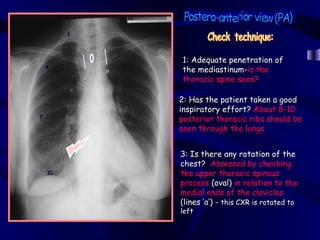

1

1: Adequate penetration of

4

a   the mediastinum-is the

a       thoracic spine seen?

2: Has the patient taken a good

inspiratory effort? About 8-10

7

posterior thoracic ribs should be

seen through the lungs

3: Is there any rotation of the

chest? Assessed by checking

10               the upper thoracic spinous

process (oval) in relation to the

medial ends of the clavicles

(lines ‘a’) - this CXR is rotated to

left

1 1: Adequate penetration of 4 a the mediastinum-is the a thoracic spine seen? 2: Has the patient taken a good inspiratory effort? About 8-10 7 posterior thoracic ribs should be seen through the lungs 3: Is there any rotation of the chest? Assessed by checking 10 the upper thoracic spinous process (oval) in relation to the medial ends of the clavicles (lines ‘a’) - this CXR is rotated to left